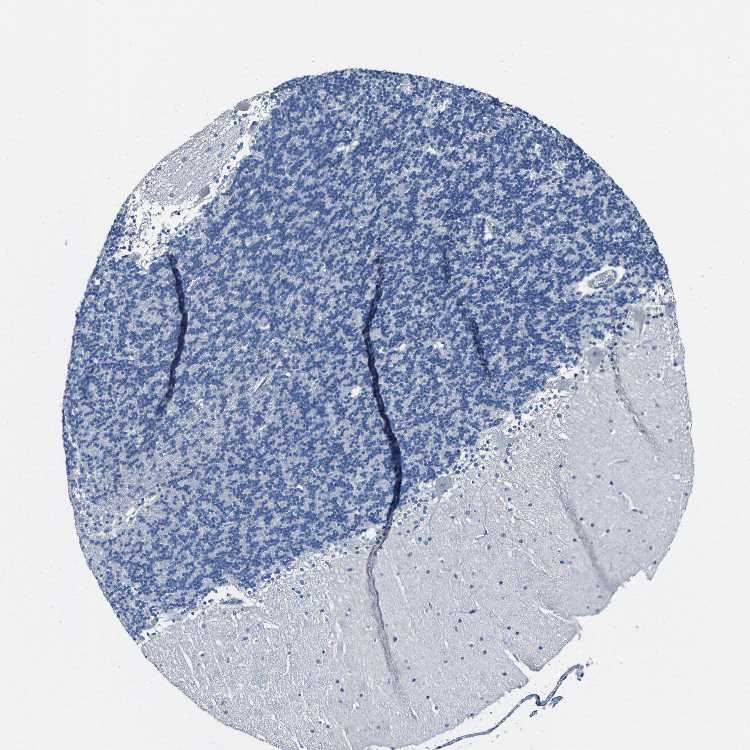

CEREBELLUM - Antibody stainingi

Antibody staining in the annotated cell types in the current human tissue is reported as not detected, low, medium, or high, based on conventional immunohistochemistry profiling in selected tissues. This score is based on the combination of the staining intensity and fraction of stained cells.

Each image is clickable and will lead to virtual microscopy that enables deeper exploration of all samples and also displays staining intensity scores, fraction scores and subcellular localization as well as patient and tissue information for each sample.

Antibody HPA013819

Purkinje cells Not detected

Cells in granular layer Not detected

Cells in molecular layer Not detected